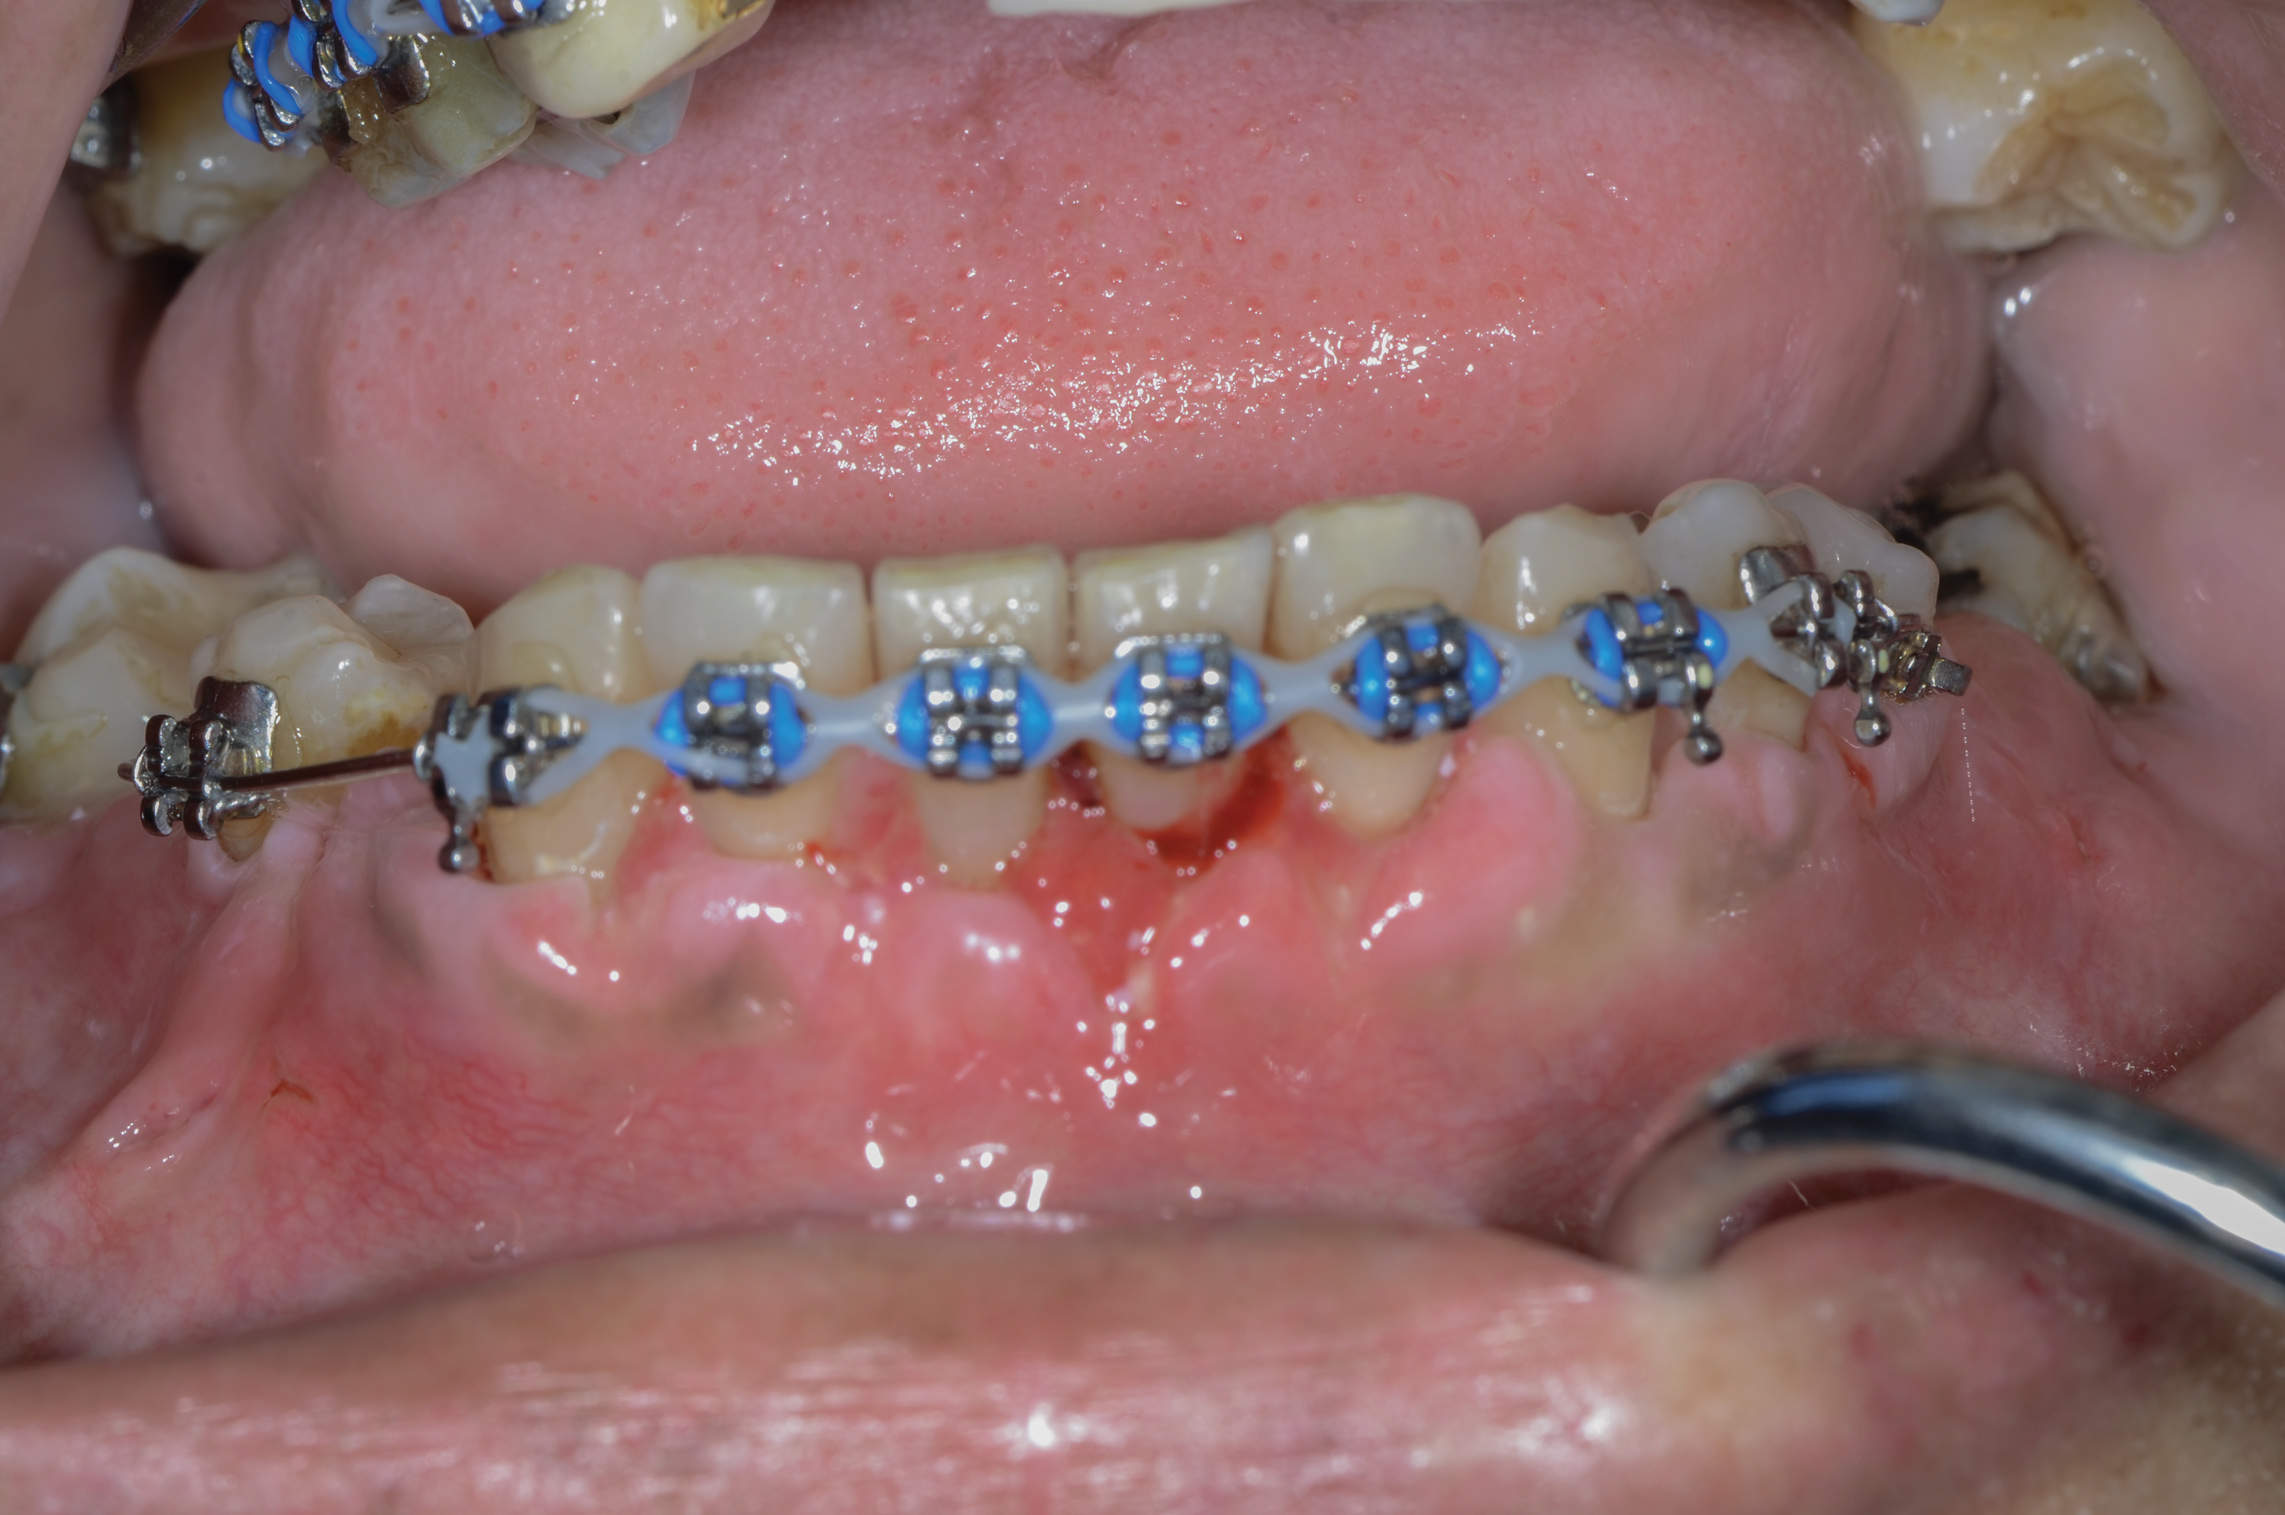

Fig 9. SFOT intraoperative surgical photograph; note the correlation of the CBCT scan in Fig 7 with the surgical findings, confirming the lack of blood supply even after completion of corticotomies.

Figure 9

Fig 7. CBCT taken before SFOT treatment; note the lack of trabecular bone in the anterior mandibular region, suggesting a lack of available blood supply.

Figure 7

Fig 8. CBCT taken 11 months after SFOT; note the minimal bone thickness gained.

Figure 8